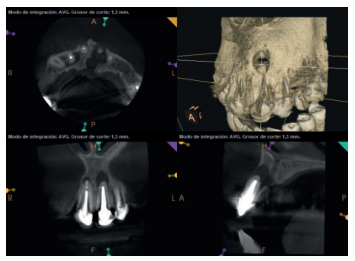

Para confirmar el origen endodóntico y el tamaño de las lesiones se realizaron exploraciones tomográficas con espesor de corte de 75 micras mediante CBCT CS8100 (Carestream Dental® ) en las que se evidenciaron lesiones periapicales radiolúcidas a nivel de 12, 11, 21 (con afectación bicortical), 25 y raíces vestibulares de 26 (Figuras 4 a 8).